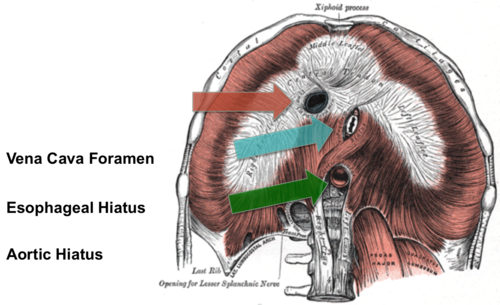

Foramen venae cava

röd pil

Hiatus aorticus

grön pil

Hiatus esophagus

blå pil